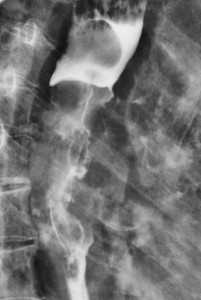

При постановке диагноза мезотелиомы перикарда используются данные рентгенографии грудной клетки, мультиспиральной КТ, магнитно-резонансной томографии сердца, ПЭТ, пункции перикарда с морфологическим исследованием экссудата, торакоскопии. Дополнительно проводятся электрокардиография, эхокардиография, радиоизотопное сканирование сердца.

Рентгенография грудной клетки при мезотелиоме перикарда помогает выявить наличие выпота и его причину - опухоль; КТ и МРТ сердца - оценить наличие и глубину инвазии опухолевого процесса: прорастание злокачественного новообразования в ткани сердца или органы грудной клетки. Большинство мезотелиом ПЭТ-позитивны, поэтому в последнее время для выявления этих опухолей часто применяют ПЭТ сердца с фтордезоксиглюкозой для определения микрометастазов в области перикарда.

Контактные метастазы представлены мягкотканным объемным образованием, прорастающим из сопредельного органа. Это может быть пищевод, трахея, гортань, реже опухоль исходит из плевры (мезотелиома), диафрагмы, ребер, позвонков.

Пример контактного распространения опухоли: мезотелиома плевры, прорастающая в верхнюю легочную долю и грудную стенку. Спиральная компьютерная томография (МСКТ).